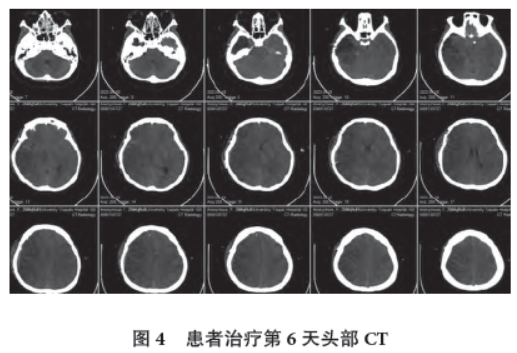

治疗第6 天,患者仍为昏迷状态,刺激无反应,脑电图左侧额颞区4~6 Hz θ 活动,双侧后头部、中线区低波幅12~14 Hz β 活动,余导联电压减低(图3),头部CT 见双侧半球脑水肿,脑白质密度增高,沿脑沟走形,右侧半球著(图4)。